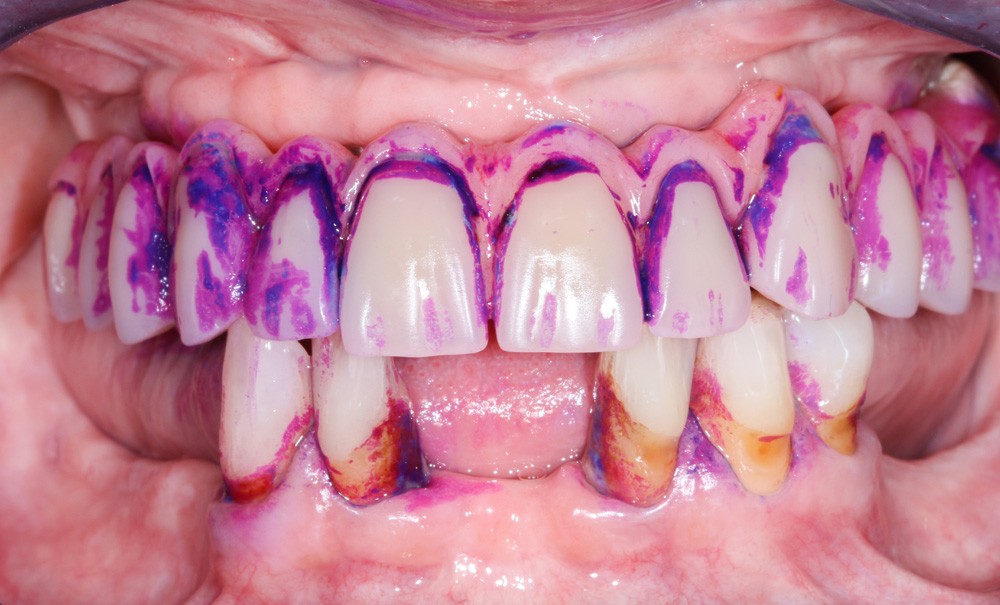

Enfin, la conception prothétique elle-même est à réfléchir, que ce soit en termes de profil d’émergence [18, 19] (pas de surcontour par exemple) (fig. 8) que d’accès à l’hygiène [20, 21] (fig. 9).